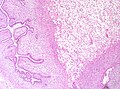

Gross

- Clefts/leaf-like structures.

- Friable - especially vis-à-vis a fibroadenoma.

Image:

Micro

The sections show a well-circumscribed mass with a leaf-like architecture. There is no stromal overgrowth or atypia. Proliferative activity is not readily apparent.